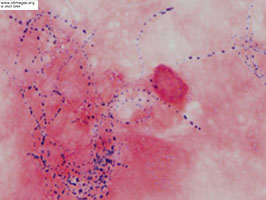

The right calf abscess fluid demonstrated beaded branching gram positive rods on gram stain (Figure 5). Kinyoun stain of leg aspiration demonstrated weakly acid-fast rods (Figure 6). Cultures were notable at 48 hours for chalk white colonies on buffered charcoal yeast abstract (BCYE) (Figure 7) and gram stain revealed branching gram-positive rods. Sanger sequencing of the 16S ribosomal rRNA gene revealed 99% similarity to Nocardia arthritidis. Cell free DNA sequencing of plasma (Karius TestTM) also yielded Nocardia but was unable to distinguish between the following species: Nocardia exalbida, Nocardia gamkensis, Nocardia arthritidis.

- Figure 6: Kinyoun stain of right calf abscess fluid - demonstrates weakly acid-fast rods.